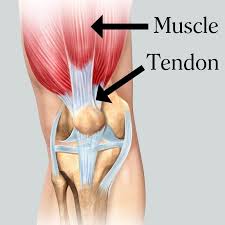

Le tendon est un élément important de l’unité musculotendineuse. Il est l’intermédiaire entre les fibres musculaires et la surface osseuse.

Les tendons ont pour fonction :

- de stabiliser par intermittence des articulations osseuses (tandis que les ligaments offrent une stabilité permanente) avec l’aide du muscle auquel ils sont liés.

- de transmettre les forces musculaires aux pièces osseuses. Le tendon et le muscle forment une composante dynamique qui permet le mouvement. Bien qu’un tendon soit peu vascularisé, on y trouve d’innombrables nerfs fournissant une information précise sur la charge tractée ainsi que sur la position du membre auquel il est attaché.